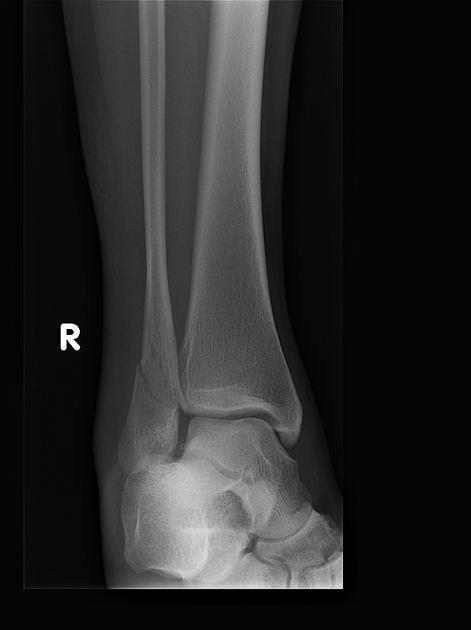

(Справа) MPT PDBИ, режим подавления сигнала от жира, аксиальный срез: у этого же пациента определяется разрыв передней и задней синдесмовидных связок ПБМС. Малоберцовая кость смещается латеральнее своего нормального положения. (Слева) Рентгенография в передне-задней проекции: определяется поперечный перелом головки малоберцовой кости с отсутствием смещения. Другие патологические изменения не определяются. Эти признаки свидетельствуют о варусной деформации и должны повысить подозрение по поводу несостоятельности малоберцовой коллатеральной связки.

2. Рентгенография при переломе проксимального большеберцово-малоберцового сустава и проксимального отдела малоберцовой кости:

• Перелом:

о Светлая линия перелома в головке, шейке или проксимальном диафизе малоберцовой кости:

- Простой или оскольчатый

- ± сопутствующий перелом латеральной верхней суставной поверхности большеберцовой кости

- ± травма Мезоннева лодыжки

• Вывих:

о Нормальная анатомия:

- Передне-задняя проекция: головка малоберцовой кости находится выше латерального кортикального слоя большеберцовой кости

- Латеральная проекция: только часть головки малоберцовой кости выступает через задний кортикальный слой большеберцовой кости

о Переднебоковой вывих:

- Передне-задняя проекция: головка малоберцовой кости визуализируется с минимальным перекрытием большеберцовой кости или его отсутствием

- Боковая проекция: головка малоберцовой кости смещается кпереди, находясь полностью выше большеберцовой кости

о Заднемедиальный вывих:

- Передне-задняя проекция: головка малоберцовой кости находится за большеберцовой костью

- Боковая проекция: головка малоберцовой кости выступает кзади от большеберцовой кости

о Верхний вывих:

- Верхний вывих головки малоберцовой кости при котором шиловидный отросток находится на уровне коленного сустава